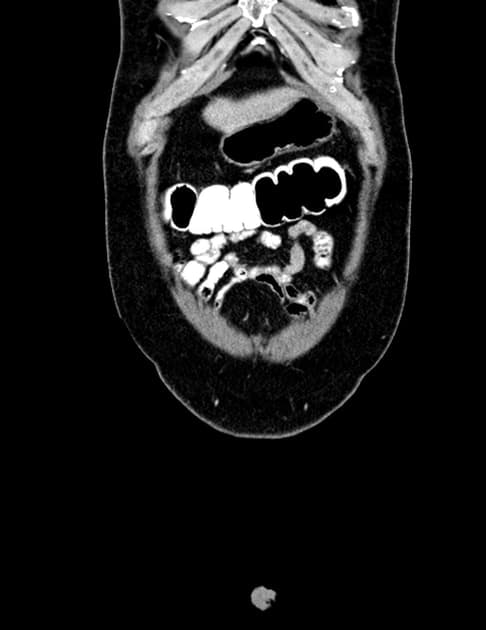

Có các dấu hiệu viêm hoạt động ảnh hưởng đến đoạn cuối ruột non và đoạn đầu ruột già: dày thành ruột (mural thickening), phù (edema), hạn chế khuếch tán (restricted diffusion) và tăng quang sau tiêm thuốc đối quang ở đoạn cuối 30 cm của ruột non và manh tràng (cecum). Mô hình tăng quang có dạng mục tiêu (targetoid), với tăng quang ở lớp niêm mạc và thanh mạc. Trong đoạn ruột bất thường này, có các đoạn ngắn không bị tổn thương, tại đó thấy các túi nhỏ ở bờ đối mạc tràng (anti-mesenteric border sacculation). Phía trên đoạn bệnh lý, có hiện tượng giãn nhẹ. Ngoài ra, ghi nhận sự tăng sinh mỡ ở vùng hạ vị phải, làm tách biệt các quai ruột bị bệnh khỏi các quai ruột còn lại trong ổ bụng. Có thể thấy hình ảnh hình thành đường rò giữa hồi tràng và manh tràng liền kề. Có nhiều hạch bạch huyết viêm trong mạc treo ruột non. Không thấy hình ảnh (no evidence of) tổn thương ở ruột non đoạn gần hoặc các đoạn khác của đại tràng. Các đoạn ruột viêm có nhu động giảm. Không thấy hình ảnh dịch tự do hoặc ổ dịch trong ổ bụng hay tiểu khung.

Hình ảnh cho thấy các đặc điểm điển hình của bệnh viêm hoạt động, bao gồm dày thành ruột và phù, tăng quang dạng lớp (layering enhancement), hạn chế khuếch tán, mỡ bao quanh (fat wrapping), và tạo túi giả dọc theo bờ đối mạc tràng. Ngoài ra, có bằng chứng của bệnh lý xuyên thành (transmural disease) với hình thành đường rò giữa hồi tràng và manh tràng.

Bệnh Crohn với tình trạng rò ruột – đại tràng (enterocolic fistulation)

- "Đường rò ruột – đại tràng giữa hồi tràng và manh tràng là biến chứng của bệnh Crohn xuyên thành."